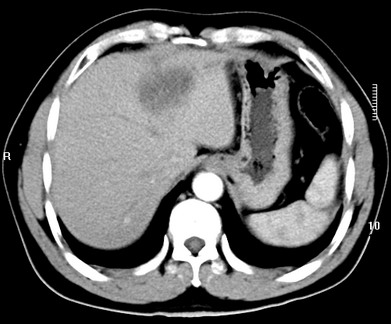

标题: CT19720:肝右叶血管瘤。肝左叶内侧段病灶考虑什么? [打印本页]

标题: CT19720:肝右叶血管瘤。肝左叶内侧段病灶考虑什么?

男,48岁,肝区不适月余,伴隐痛。

支持右叶血管瘤,左叶病灶考虑肝腺瘤。

1)不排除肝左叶肝癌。2)肝右叶血管瘤。

肝左叶炎性病变,肝癌待排。2)肝右叶血管瘤。

1.肝右叶血管瘤;2.肝左叶炎性假瘤?肝癌?建议穿刺活检.

右叶病灶典型,左叶病变慢性炎块

1、肝右叶血管瘤(典型)。

2、肝左叶病灶,强化不明显,疑炎性假瘤,建议结合临床并密切随访。

1、肝左叶炎性病变,肝癌待排。

2、肝右叶血管瘤。

肝左叶脓肿,肝癌待排。2)肝右叶血管瘤